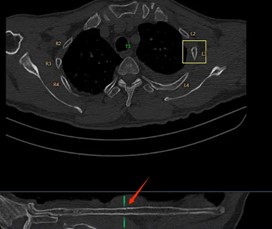

在一些大型医院和医疗研究机构,已经开始尝试这种协作模式。例如,在胸部CT肺结节以及肋骨骨折的影像诊断中,AI 首先对影像进行分析,标记出可能的异常区域,医生再对这些区域进行详细观察和诊断。通过这种协作,不仅提高了诊断效率,还提升了诊断的准确性。